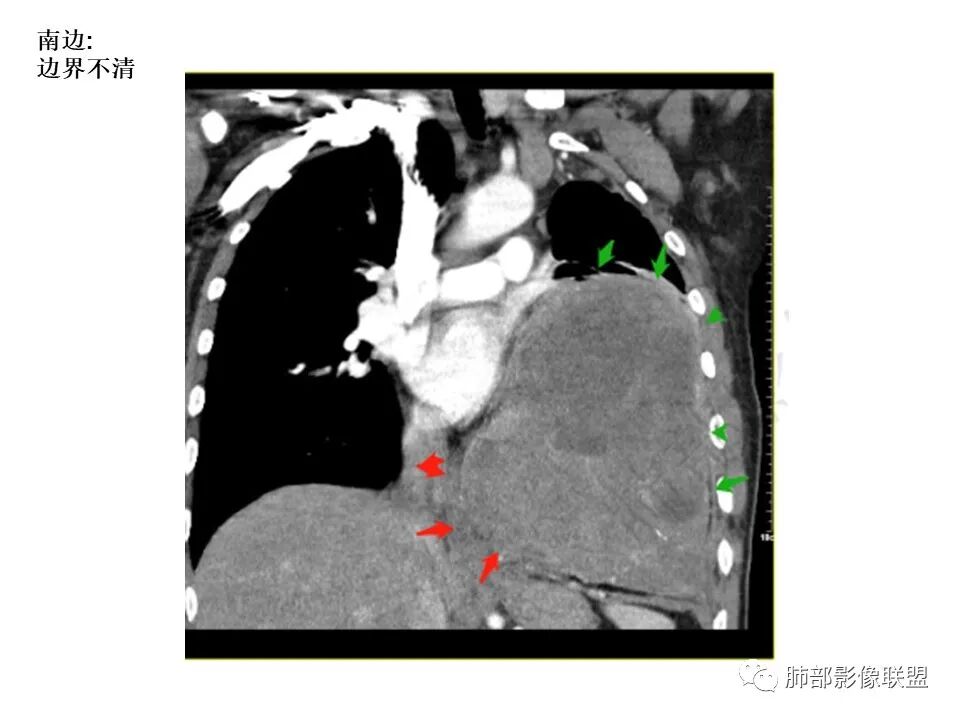

南边:

还是支持脏层胸膜来源SFT首选,其次肺内肉瘤

因为:

1局部胸膜起源,所以与胸膜分界不清

2、肺内病变,局部胸膜侵犯

如果胸膜侵犯,局限在这里,而且支气管侵犯不是很明显,似乎不合理

内部坏死都可以,钙化,SFT几率高一些